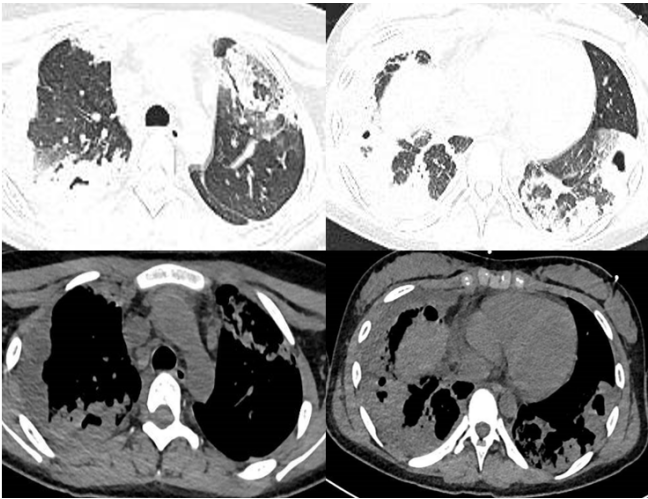

患者女性,15岁,学生。主诉:咳嗽咳痰10天,发热1周,呼吸困难4天。诊断为重症支原体肺炎,重度ARDS。

图片

予患者高流量氧疗、无创通气、气管插管有创通气、俯卧位,但其低氧血症和高碳酸血症均无法纠正,最终启动VV-ECMO,整体治疗效果较好。7天后撤机。但患者并发泛耐药鲍曼不动杆菌肺脓肿脓胸,胸水浑浊,胸水培养和BALF培养均为泛耐药鲍曼不动杆菌。

经过反复胸腔闭式引流,多黏菌素B+替加环素(21天)/多西环素+美罗培南(8天)抗感染,患者好转出院,出院后1个月和4个月复查肺部CT,可见病灶吸收良好。尽管如此,院内感染仍然延长了患者的住院时间,增加了医疗费用。因此,ECMO救治过程中一定要警惕并发症的发生。